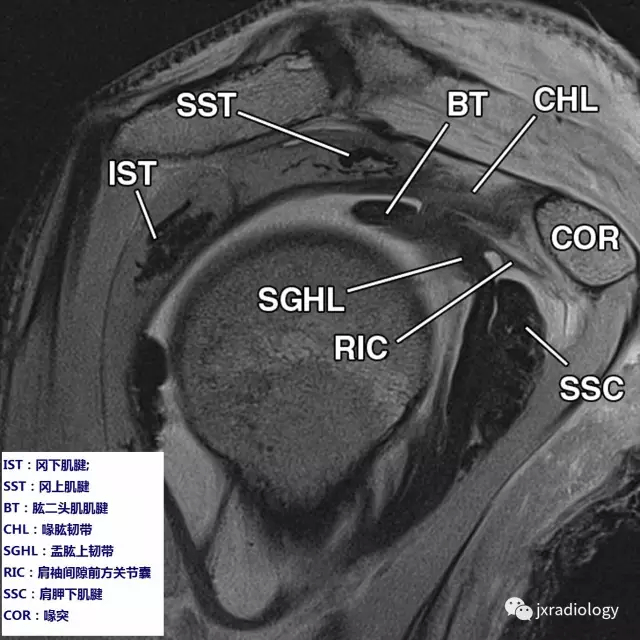

肩袖mri解剖图

肩袖间隙的解剖及常见病变